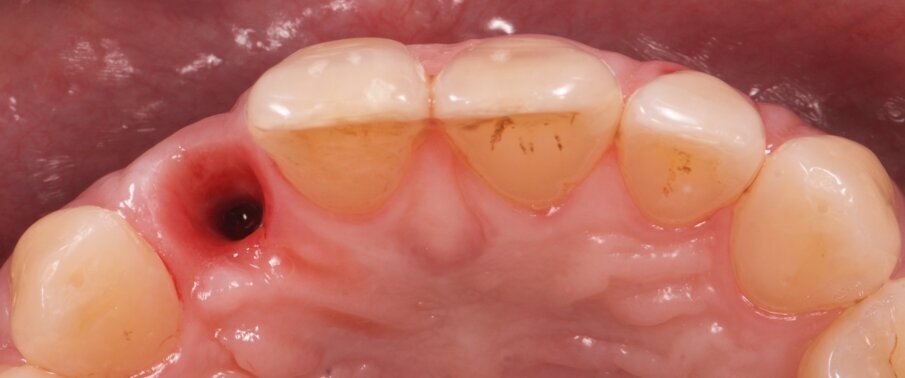

Fig. 3: Clinical view after extraction of fractured tooth #22.

Fig. 8: Clinical situation after four months of healing after removal of the provisional restoration.

Fig. 9: Clinical view after removal of the provisional restoration and placement of a customised impression coping replicating the emergence profile of the temporary crown.

Fig. 10: Clinical situation one month after placement of the definitive restoration. Note the preservation of the tissue volume and the gingival margin.